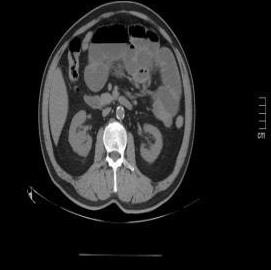

• 超声内镜引导下胃旁曲张静脉精准断流术治疗食管胃静脉曲张出血的疗效分析(附20例报告)

2025, 31(8):85-90. DOI: 10.12235/E20250036

摘要 (153) HTML (42) PDF 5.38 M (98) 评论 (0) 收藏

摘要:目的 探讨超声内镜引导下胃旁曲张静脉精准断流术治疗食管胃静脉曲张出血的疗效。方法 回顾性分析2024年1月1日-2024年12月31日于该院接受超声内镜引导下胃旁曲张静脉精准断流术治疗的20例肝硬化食管胃静脉曲张出血患者的临床资料,并评估治疗效果。结果 20例患者均顺利完成超声内镜引导下胃旁曲张静脉精准断流术;注射组织胶联合置入弹簧圈(16例)和单独注射组织胶(4例)均成功阻断胃旁来源的曲张静脉;所有患者均未发生穿孔、食管贲门狭窄、大出血、败血症和异位栓塞。1例单独注射组织胶的患者,术后胃旁曲张静脉少许渗血,经降低门静脉压力治疗3 d后好转,另1例单独注射组织胶患者,术后出现低热,抗感染3 d后体温恢复正常。结论 超声内镜引导下胃旁曲张静脉精准断流术治疗食管胃静脉曲张出血的临床疗效好,异位栓塞、大出血、感染和穿孔等并发症少,但仍需要密切随访,观察胃旁曲张静脉的排胶问题。